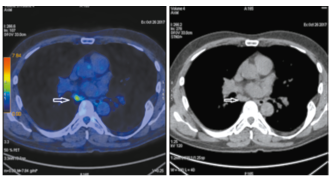

Через 32 мес пациент жив без признаков прогрессирования заболевания. По данным ПЭТ/КТ от 27.05.2020 первичной опухоли почек не выявлено (рис. 8).

Рис. 8а-8б. На корональных ПЭТ/КТ- (а) и КТ-проекциях (б) очагов повышенного метаболизма и патологических образований не выявлено. На аксиальных ПЭТ/КТ- (в) и КТ-проекциях (г) литический очаг в ножке L3 прежних размеров без фиксации радиофармпрепарата.

Fig. 8a-8b. PET/CT (a) and CT images in coronal projection did not show increased metabolism or pathological formations (b). PET/CT (c) and CT images in axial projection (d) showed lytic lesion in L3 articular process of the same size without accumulation of the radiopharmaceutical.

Рис. 8в-8г. На корональных ПЭТ/КТ- (а) и КТ-проекциях (б) очагов повышенного метаболизма и патологических образований не выявлено. На аксиальных ПЭТ/КТ- (в) и КТ-проекциях (г) литический очаг в ножке L3 прежних размеров без фиксации радиофармпрепарата.

Fig. 8c-8d. PET/CT (a) and CT images in coronal projection did not show increased metabolism or pathological formations (b). PET/CT (c) and CT images in axial projection (d) showed lytic lesion in L3 articular process of the same size without accumulation of the radiopharmaceutical.